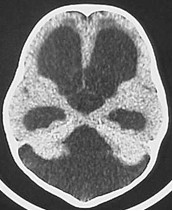

Przedstawione na rycinie badanie CT obrazuje jedną z form wodogłowia obturacyjnego. Które z poniższych twierdzeń opisujących uwidocznione w badaniu zmiany jest prawdziwe?

1) uwidocznione w badaniu CT wodogłowie obturacyjne spowodowane jest niedrożnością otworu pośrodkowego - Magendie'go i otworów bocznych-Luschki komory IV mózgu;

2) badanie przedstawia wodogłowie w zespole Arnolda-Chiariego typ II;

3) jest to typowy obraz wodogłowia w przebiegu torbieli pajęczynówki w obrębie zbiornika wielkiego;

4) wodogłowie spowodowane jest wgłobieniem migdałków móżdżku w obręb otworu wielkiego;

5) na zespół Dandy-Walkera składają się: wodogłowie, torbiel tylnego dołu czaszkowego i niedorozwój (dysgenezja) dolnego robaka móżdżku.